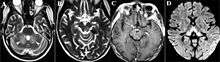

The sensitivity of MR was 53% and the specificity was 93%. The reversible cytotoxic edema was considered the most characteristic lesion of WE. The location of the lesions were more frequently atypical among non-alcoholics, while typical contrast enhancement in the thalamus and the mammillary bodies was observed frequently associated with alcohol abuse.[49] These abnormalities may include:[6]

- Medial thalami, periaqueductal gray matter, mamillary bodies, and brainstem nuclei edema (Zuccoli G.). Involvement is always bilateral symmetrical. Value of DWI in the diagnosis of WE is minimal. Axial FLAIR MRI images represent the best diagnostic MRI sequence. Contrast material may highlight involvement of the mamillary bodies.